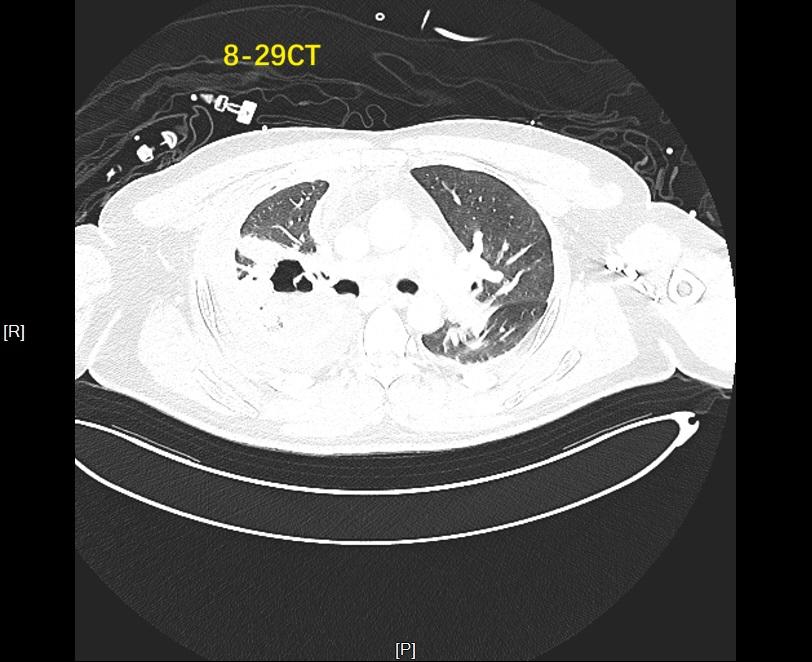

支气管胸膜瘘被称为胸外科治疗中的“硬骨头”,其瘘口周围组织常伴随炎症、血供不良等问题,且易出现复杂的气流异常,给治疗带来极大挑战。中大医院呼吸与危重症医学科副主任丁明副主任医师带领的介入团队接诊后,首先通过术前CT初步锁定右上叶后段为疑似瘘口位置,但要确保封堵精准,还需更精密的检测。

术后一周的CT复查显示,患者胸腔内气胸明显消失,上叶空洞显著缩小,顺利拔除引流管出院。术后一个月再次复查时,胸部CT证实右肺已完全复张,气胸症状彻底消失,达到临床治愈标准。